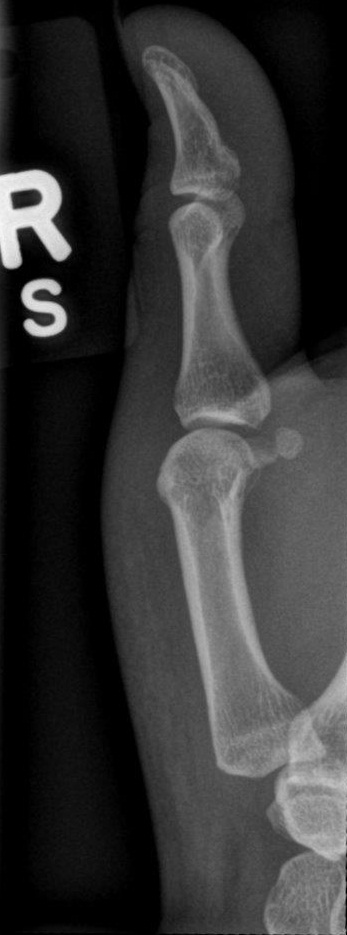

Lateral Thumb

What position is demonstrated?